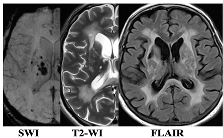

| F3 MRI Type 1 | F3 MRI Type 2 |

![]() | ![]() |

| WMH: more pronounced in the periventricular and deep regions of the cerebral hemispheres, subcortical structures, external capsule, brainstem, and cerebellum | WMH: periventricular—in the posterior cerebral hemispheres, deep—in the frontal and parietal lobes |

| Lacunes: multiple in subcortical structures and cerebral white matter | Lacunes: single in the white matter of the cerebral hemispheres |

| CMB: juxtacortical CMHs in all regions of the cerebral hemispheres, in subcortical structures | CMB: single juxtacortical CMHs in the white matter of the temporal and parietal lobes |

| Cerebral atrophy: more pronounced | Cerebral atrophy: less pronounced |

| Enlarged PVS: pronounced in subcortical structures | Enlarged PVS: extended |

| Cognitive impairment: more pronounced (MCI and dementia) | Cognitive impairment: less pronounced (SubCI and MCI) |

| Gait disorders: more pronounced | Gait disorders: less pronounced |

| Reduced VEGF-A | Increased TNF-α |